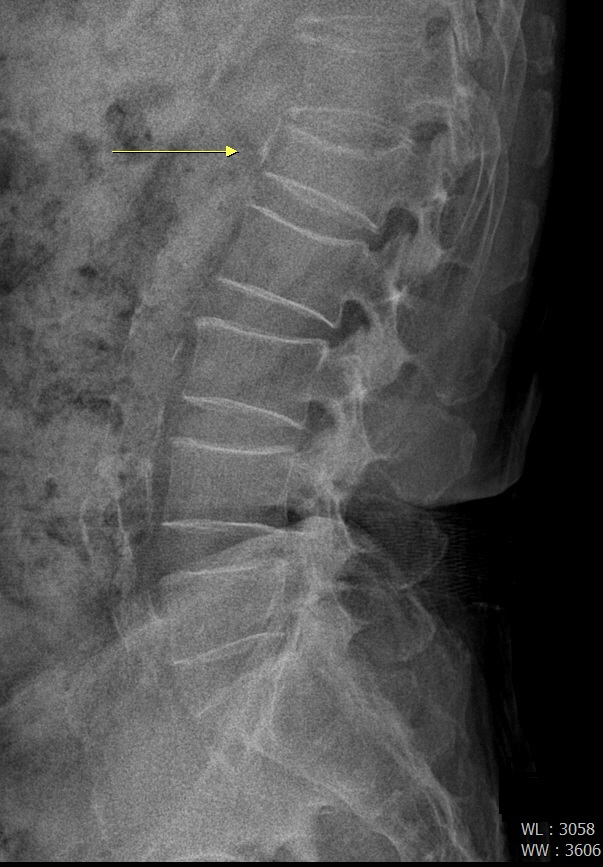

척추압박골절은 외부 충격에 의해 척추뼈가 납작하게 내려앉는 질환이다. 대부분 골밀도가 낮은 어르신들이나 골다공증이 있는 사람들이 외부에서 충격을 받을 때 발생한다.

척추압박골절이 생기면 누워있거나 앉아 있다가 자리에서 일어나려고 할 때 심한 통증을 느낀다.

기침이나 재채기를 할 때 증상이 더 심해지며, 다리 통증으로 걸음걸이가 부자연스러워 어르신들은 오리걸음을 걷기도 한다. 갑자기 부러지면서 발생한 급성 압박 골절의 경우에는 허리통증이 발생한다. 증상이 경미한 경우 단순 근육통이나 단순 허리통증으로 오인할 수 있다. 골절된 척추 뼈 주변으로 통증이 발생하는 경우가 많지만, 옆구리 방사통, 둔부 방사통, 꼬리뼈 통증이 동반되는 경우도 있다. 초기에는 요통이 강하게 느끼는 경우가 많아 환자들이 단순하게 허리를 삔 증상(염좌)으로 생각하거나 허리디스크로 오인을 하는 경우가 잦다.

서울예스병원 척추센터 하주경 센터장(신경외과 전문의)은 "척추압박골절은 등과 허리에 꼼짝할 수 없을 정도의 통증이 나타나며 가슴, 아랫배, 엉덩이까지 통증이 뻗어 나가는 것이 특징인 반면, 허리디스크의 경우 허리 통증 외에 엉치, 허벅지, 종아리, 발끝 등이 저리거나 당기는 증상을 보여 구분할 수 있다"며 "돌아누울 수 없을 정도로 허리 통증이 심하며 시간이 지날수록 몸이 점점 앞으로 굽게 된다면 척추압박골절을 의심할 수 있으니 즉시 병원을 찾는 것이 좋다"고 조언했다.

척추압박골절이 조기에 진단 및 치료가 이뤄지지 않고 장기간 방치할 경우 만성 요통을 유발하고 심폐기능까지 약해질 수 있다. 게다가 척추압박골절이 점점 진행해 척추가 앞쪽으로 휘어 등과 허리가 굽는 척추후만증이 발생할 수 있다. 또 골절된 뼈조각이 신경을 압박해 마비 등 신경 증상이 발생할 수 있다. 경우에 따라서는 골절된 뼈 내부가 녹아버리는 무혈성 괴사가 일어날 수 있어 주의해야 한다.